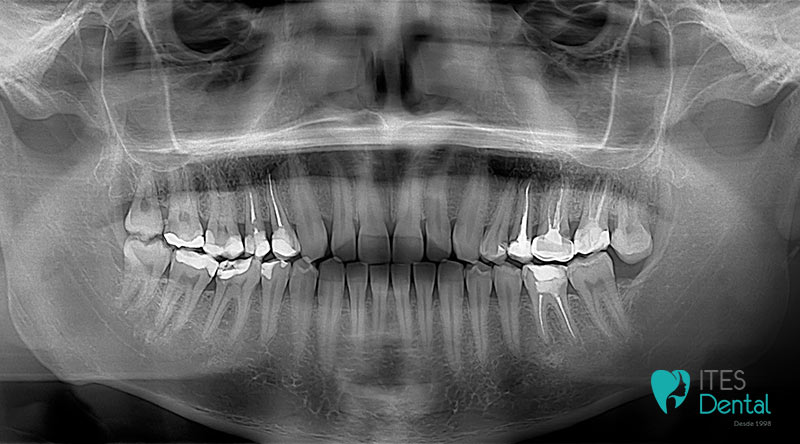

Tipos de radiografías dentales y para qué sirve cada una

| Tipo | ¿Para qué sirve? |

|---|---|

| Periapical | Ver raíz, nervio e infecciones localizadas |

| Bitewing | Detectar caries entre dientes |

| Panorámica | Visión general de boca, huesos y muelas del juicio |

| TAC dental 3D | Planificación avanzada de implantes y cirugías |